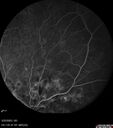

NPDR and Severe macular ischemia sudden vision loss180 views60 year old female with sudden vision loss OD 1 week ago. VA 20/63, 20/200. OCT-A and FA shows severe macular ischemia OUJan 11, 2026

NPDR and Severe macular ischemia sudden vision loss186 views60 year old female with sudden vision loss OD 1 week ago. VA 20/63, 20/200. OCT-A and FA shows severe macular ischemia OUJan 11, 2026

NPDR and Severe macular ischemia sudden vision loss174 views60 year old female with sudden vision loss OD 1 week ago. VA 20/63, 20/200. OCT-A and FA shows severe macular ischemia OUJan 11, 2026